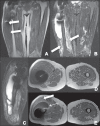

Soft tissue complications following hip arthroplasty may occur either in cases of total hip arthroplasty or in hip resurfacing, a technique that has become popular in cases involving young patients. Both orthopedic and radiological literatures are now calling attention to these symptomatic periprosthetic soft tissue masses called inflammatory pseudotumors or aseptic lymphocytic vasculites-associated lesions. Pseudotumors are associated with pain, instability, neuropathy, and premature loosening of prosthetic components, frequently requiring early and difficult reoperation. Magnetic resonance imaging plays a relevant role in the evaluation of soft tissue changes in the painful hip after arthroplasty, ranging from early periprosthetic fluid collections to necrosis and more extensive tissue damage.